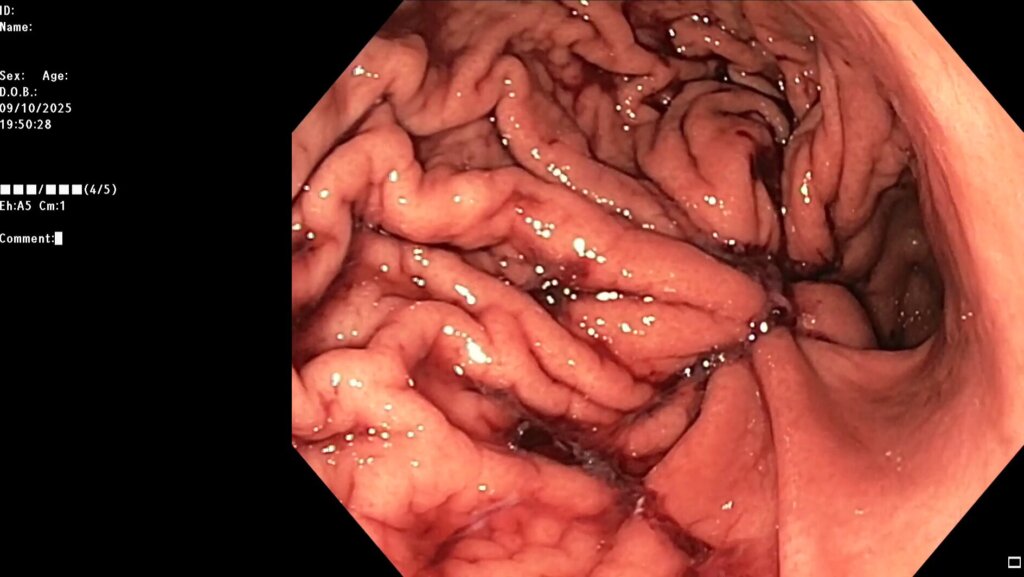

После предварительного обследования произведена операция: ESG + АПК (APC) свода; всего использовано 6 швов, время процедуры ≈ 120 минут.

Под видеоконтролем выполнена эндоскопическая рукавная гастропластика: сшивание стенок желудка при помощи аппарата Overstitch Boston Scientific по длине тела с целью уменьшения объёмов съедаемой пищи.